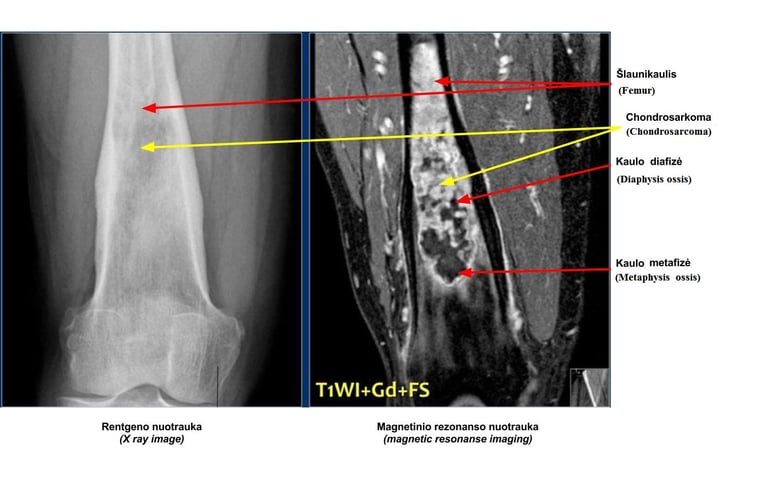

Kondrosarkom tanısı genellikle bir dizi klinik ve görüntüleme yöntemi kullanılarak konur. İlk adım hastanın tıbbi geçmişinin ve semptomlarının dikkatli bir değerlendirmesidir. Daha sonra fizik muayene ile tümörün büyüklüğü ve yerleşim yeri belirlenir. Kondrosarkomlar benign (iyi huylu) kıkırdak tümörleri ile karıştırılabilir, Tanıda en önemli adım görüntüleme çalışmalarıdır. Röntgen, manyetik rezonans görüntüleme (MRG), bilgisayarlı tomografi (BT) ve pozitron emisyon tomografisi (PET) gibi yöntemlerle tümörün yerini ve özelliklerini belirlemek için detaylı görüntüler elde edilir. Tanı kesinleştirmek için bir biyopsi yapılır, bu işlem sırasında tümörden doku örnekleri alınır ve patolojik inceleme ile tümörün malign (kötü huylu) olduğu ve kondrosarkom olduğu onaylanır. Patolojik inceleme aynı zamanda tümörün ne kadar agresif olduğunu da belirler, bu da tedavi seçeneklerini etkileyebilir. Kondrosarkom tanısı ve sınıflandırılması genellikle bir multidisipliner yaklaşım gerektirir ve bir onkolog, ortopedist, radyolog ve patolog tarafından birlikte değerlendirilir.

Resim 3. Kondrosarkom tanı sürecinde düz grafi, MR ve biyopsi yapılır.